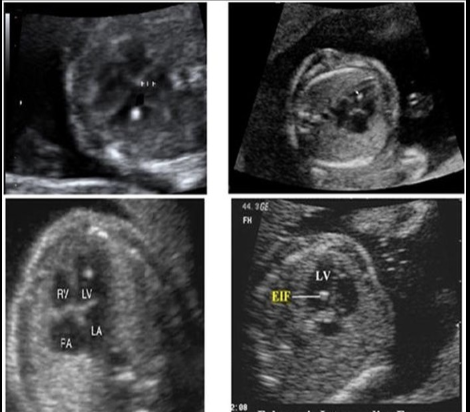

trisomy 13 is suspected

a) A

b) B

c) C

d) D